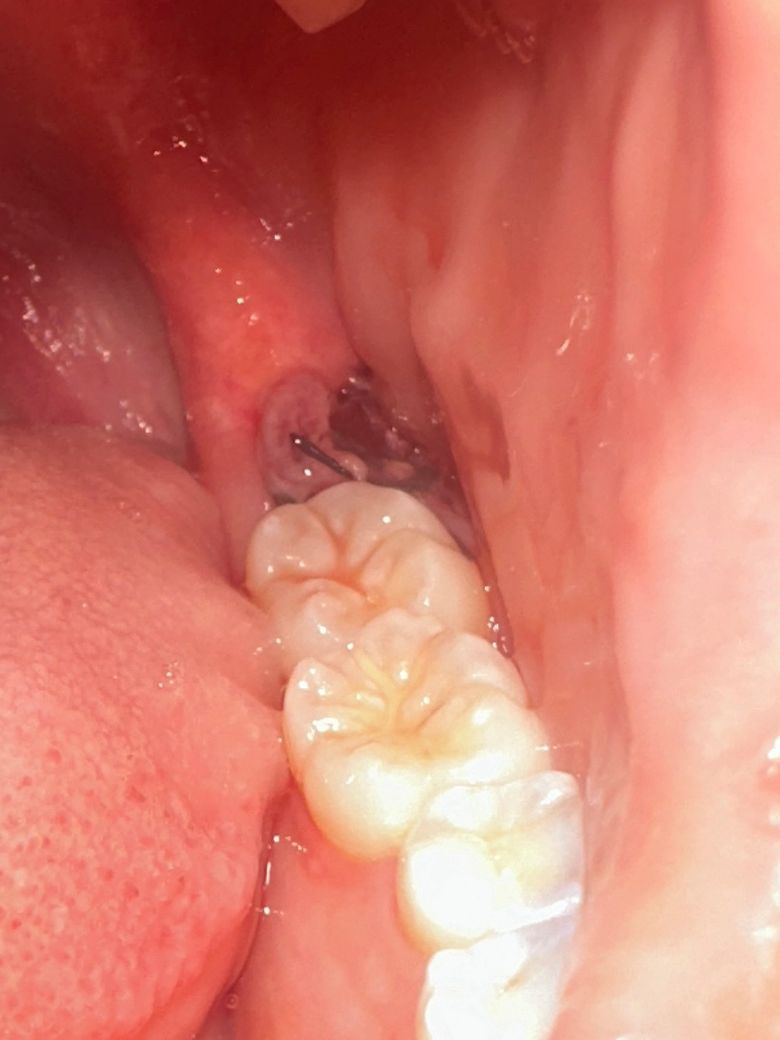

사랑니 발치 2일차에 소리지른 후 사진입니다 괜찮은건가요?

첫번째는 소리지른 후 사진이고 두번째는 소리지르기 전 사진입니다 아무 차이 없어 보이나요?? 흰색이 좀 작아진거같은데... 잘 아물고 있는건가요?

사진상으론 큰 문제는 없어보입니다 소리를 지른거 자체보다는 입을 너무 크게벌리거나 하면 잇몸 아문부위가 벌어질 수 있습니다